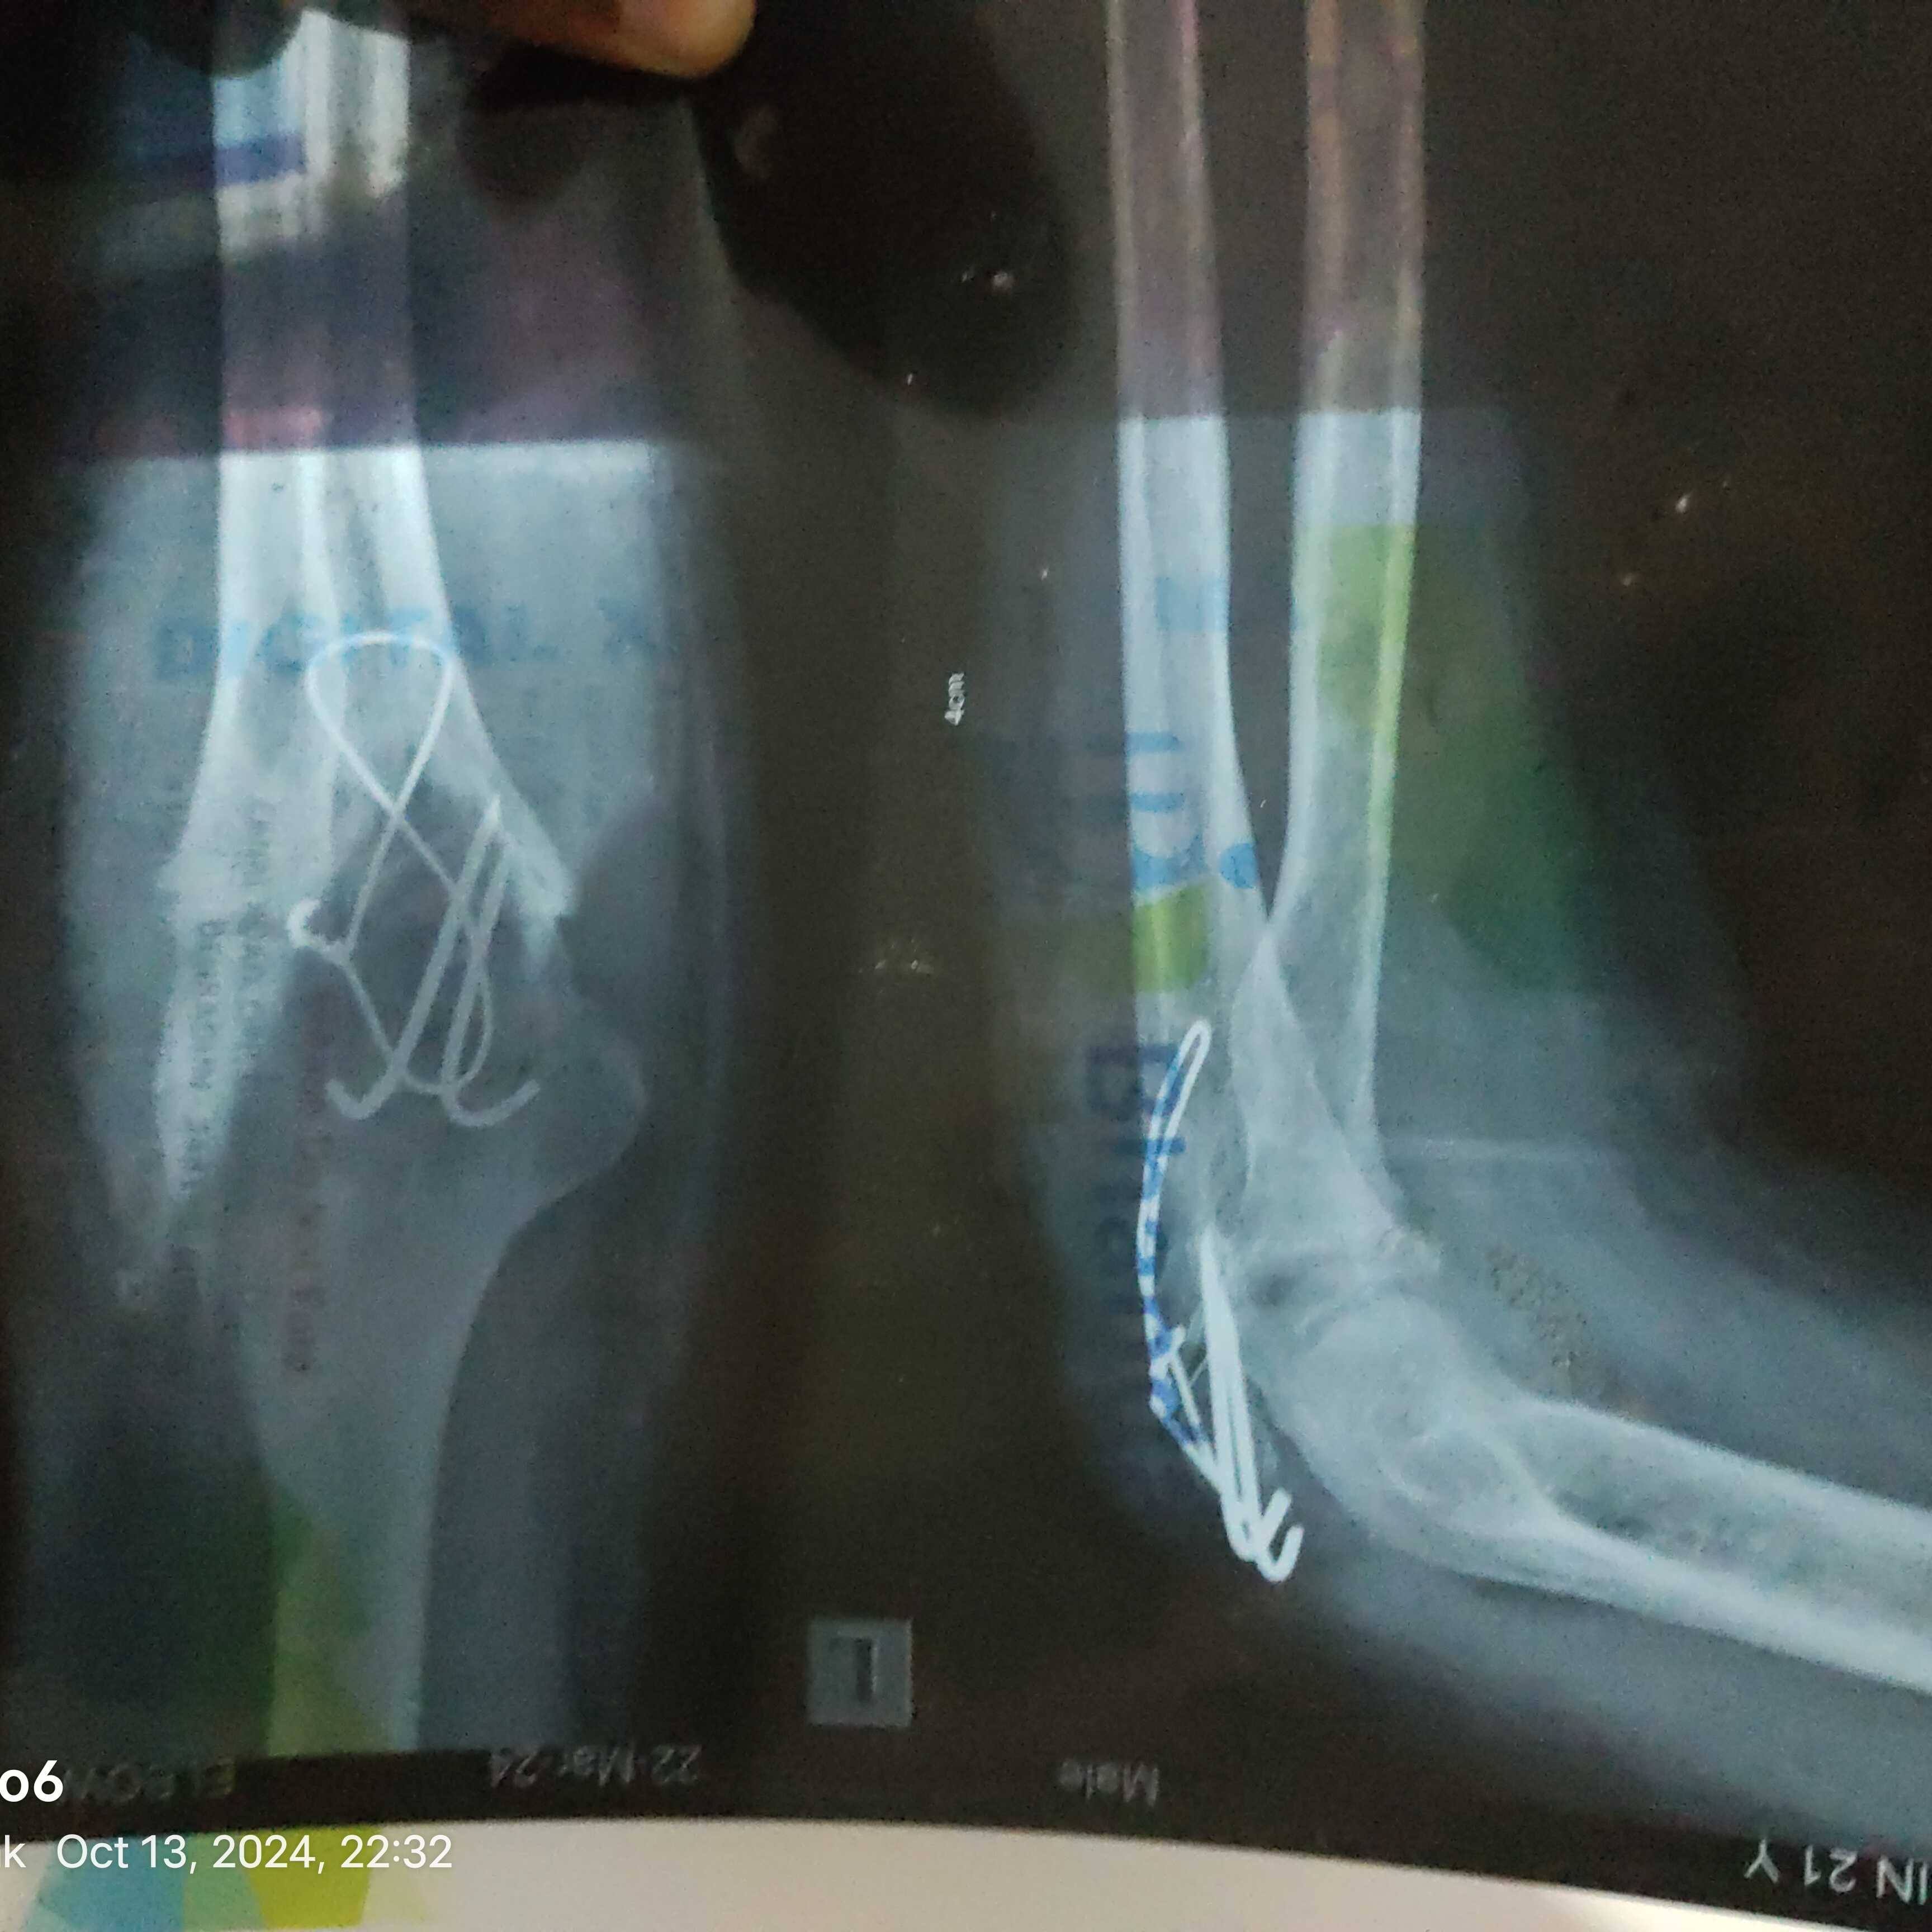

sir kya mera elbow replacement possible hai?

Mera left elbow poora jaam ho chuka hai...naa mudtaa hai naa sidha hota hai aur abhi March mai Mera left elbow ka operation hua tha...Dr ne joint ko bs wire se jod diya hai...aur abhi meri bone tb ki medicine chal rhi hai

sir mera elbow replacement possible hai ?

Mera elbow jaam ho gya hai mera haath nhi mudtaa bilkul nhi..aur naa hi sidha hota hai....March mai operation hua tha..Dr ne joint ko wire se jod diya hai bs....abhi bone tb ki dawaai chal rhi hai meri